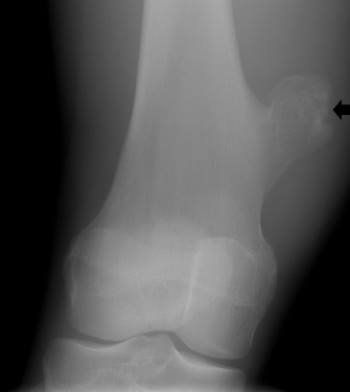

Chủ đề U xương chày lành tính

Xạ hình xương có phải phương pháp xác định u xương chày lành tính hay ác tính không?

Bác sĩ ơi, em con được chẩn đoán lâm sàng: U xương chày phải và được các bác sĩ ở bệnh viện chỉ định xạ hình xương toàn thân ạ. Vậy bác sĩ cho con hỏi xạ hình xương có phải xác định u xương chày lành tính hay ác tính không ạ? Nếu là ung thư xương thì có cách nào điều trị được không ạ? Tỉ lệ thành công điều trị bệnh như thế nào ạ. Con cảm ơn bác sĩ ạ.